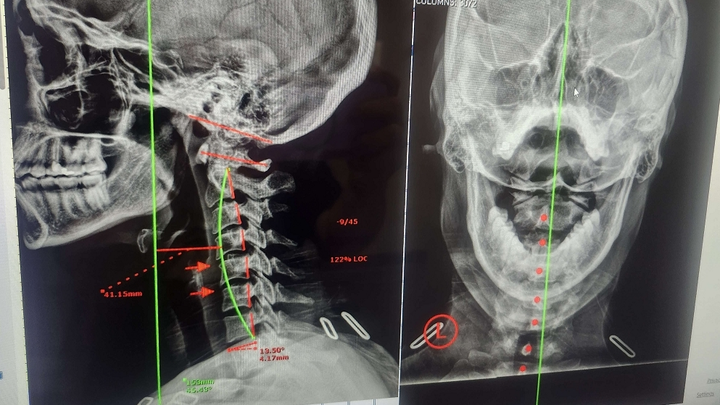

I've had back pain for a while but didn't amount it to anything. I told myself that I have poor posture and I need to work on that and it'll get better. I've been to a chiropractor and they didn't find anything, adjusted me and I was on my way but the situation never resolved itself. I decided to ask my co-worker for their chiropractor and it turned things around for me, both in good and bad ways. I discovered that my spine is curved and I've had scoliosis probably my whole life which is odd given all the silly exams I had growing up at the nurse's office and the doctor's office where they 'test for it'. The other situation which is far more alarming according to the chiropractor is that I lost the curvature of my neck and it's been like that for a couple decades based on how the degeneration looks and I am getting pretty close to ending up with bone on bone which means it cannot be fixed once that happens. He said that that is pulling on my spinal cord pretty bad which is making my lumbar hurt 2x as much and fixing this would make a dramatic difference.